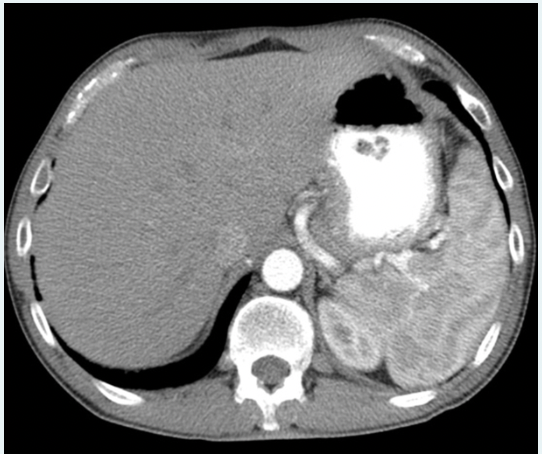

In what phase of tissue enhancement is the intravenous iodinated contrast in the image below?

a.arterial

b.3 hours post drinking oral contrast media

c.3 hours post injection

d.portal venous

A